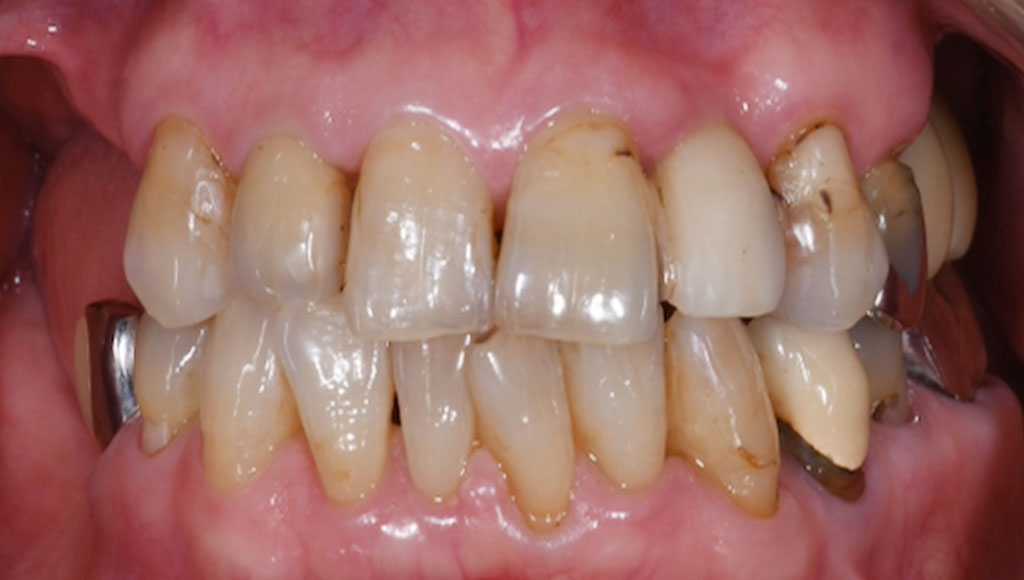

前歯(右123番)ジルコニアブリッジによる審美治療

Before

After

セットしたジルコニアブリッジ

患者様の主訴

70代女性。横浜市在住。右上123番のブリッジが脱離し、ブリッジが合わないため、ジルコニアかインプラントにするか迷い、来院。

診断結果

ジルコニアブリッジを装着するために元のブリッジを外し、歯の形成を行いジルコニアブリッジをセット

治療内容

ジルコニアブリッジを装着するために元のブリッジを外し、歯の形成を行い光学印象(プライムスキャンによる)型取りを行いました。光学印象のデータを元に当院の院内技工室にてデジタル加工を行い、ジルコニアブリッジを作成し、セットを行いました。

治療期間

2回

治療費用

総額:330,000円(税込)

◼️内訳

ジルコニアクラウン:110,000円(税込)/1本×3本

光学印象(プライムスキャン)

リスク・副作用

補綴物の脱落・欠落、咬合違和感、色調補正